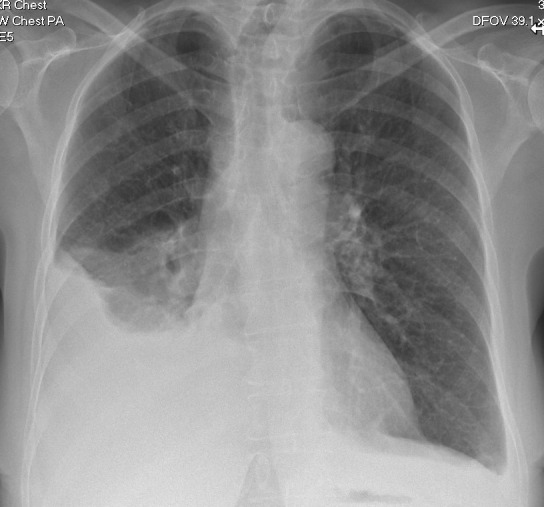

Bilateral pleural effusions, ascites and pulmonary emboli: Meigs syndrome.

Meigs syndrome is associated with unilateral or bilateral pleural effusions, ascites, high CA-125 levels and ovarian fibromas. Concurrent arterial and venous thromboses have also been described. Surgical removal of the fibroma is curative. https://bit.ly/4jZsB4D.